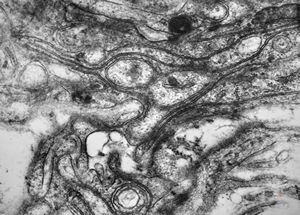

M,15y. | neurinoma - orbita